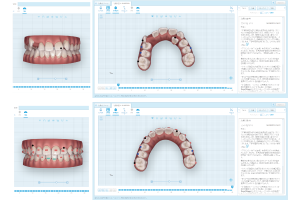

7、治療後の歯並びをイメージできる

口腔内スキャナーiTero(当院では、親しみをこめて「ペッ歯ーくん」と呼んでいます。)を導入。ペッ歯ーくんのスキャナーで、お口の中を撮影すると、すぐにモニターに歯列が表示されます。今までのような歯の型をとることなく、その場で歯並びの現状と問題点を把握することがができます。

専用のシミュレーションソフトで、治療中の歯が動き見ることができ、治療終了のイメージも確認することができます。